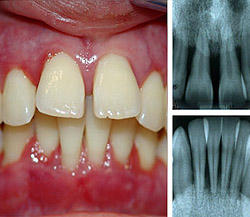

Клиническая картина пародонтоза: оголение шеек зубов (часть зуба около десны) и корней, рецессия (опущение) десен, [4] зуб становится «вытянутым», при этом воспаление, отечность и кровоточивость отсутствует, цвет десны бледно-розовый (может быть бледнее цвета здоровой десны), десна плотно охватывает зуб (в отличие от воспалительного заболевания тканей пародонта – гингивита и пародонтита).

Средняя степень пародонтоза характеризуется оголением шеек зубов и корней (до 3мм), на рентгеновском снимке можно заметить снижение высоты костных перегородок между зубами, достигающее половины высоты корней зубов. Пациенты могут жаловаться на появление неприятных ощущений в деснах, зуда, на изменение положения зубов (наклон, смещение в виде веера).

При тяжелой степени пародонтоза оголение шеек зубов и корней доходит до 5 мм, костные перегородки разрушены уже на 2/3 длины корней зубов, что приводит к появлению подвижности зубов и изменению их положения в челюсти и смыкания между собой.

Если глубина зазора не более 3мм, то признаков гингивита и пародонтита нет и десна здорова, тогда как глубина зазора более 5мм свидетельствует о наличии пародонтита. Скопления зубного налета и наличие зубного камня так же учитываются при диагностике пародонтита. Для комплексной оценки состояния костной ткани челюсти показано выполнить ортопантомограмму.

- Рентген. Степень выраженности хронического пародонтита определяется на основании данных прицельной рентгенографии и ортопантомографии.